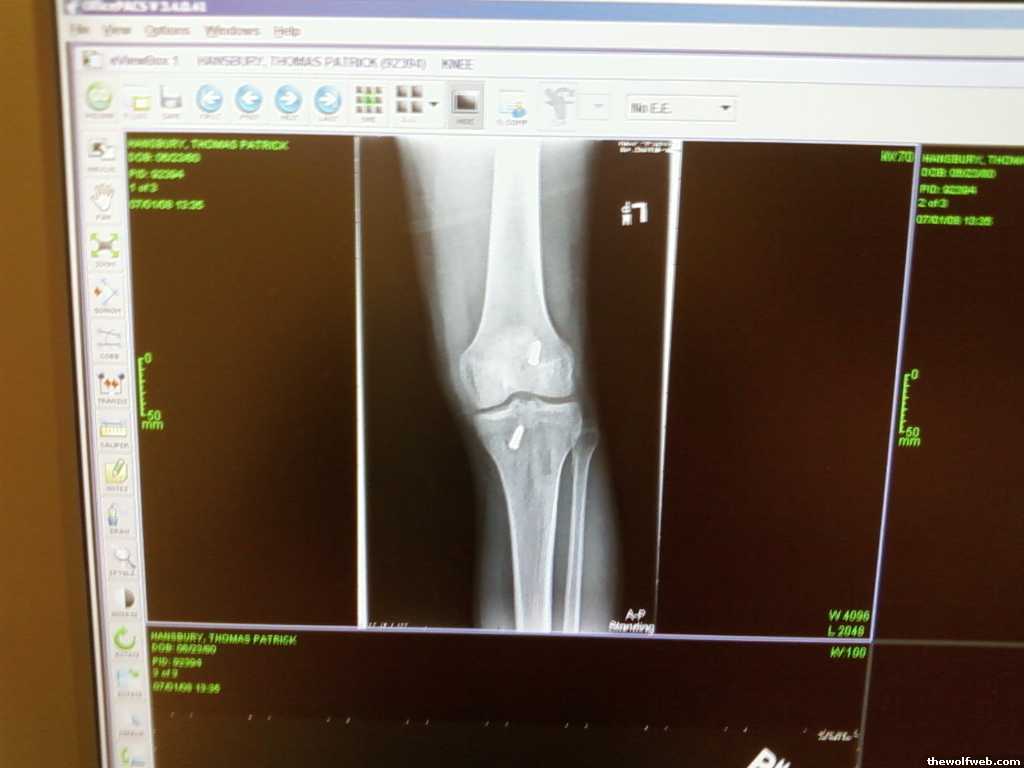

Tke, I put a picture of my knee after surgery in my gallery.

^thats a pretty crazy photo man, how many days after surgery was that? I ask b/c it looks like the swelling isn't that bad (comparatively). Those staples are rough too! I had internal stitches thank God. My therapy regiment calls for 3 visits a week (each about an hour or so long). In addition, I do exercises myself on the off days (whatever I can do without specialized equipment).

Tke, i think that was after my 1-2 wk follow up. It was the first time I had all the bandages off.